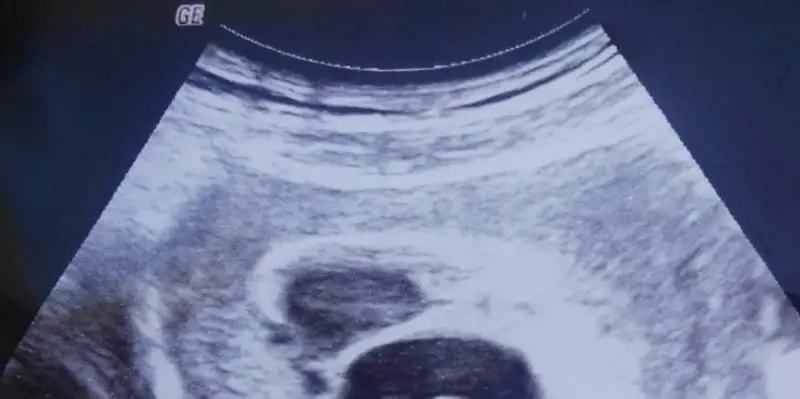

Canım kötü düşünmek yok allahın izniyle kanamanda duracak ne güzel tutunmuş bak büyüyür da moral bozmak yokKizlar lekelenmem vardi sabah doktora gittim. Kanama alanim hala duruyor isin kotu yani kan keseye damliyor. Doktor kanaman cogalabilir kritik donem dediBirde bebegim normalde gunde en az 1 mm buyuyordu ama simdi dort gunde 2 mm buyumus. Aklimi kaybetmek uzereyim Kese ve kanama alanina bakarmisiniz nasil keseye damliyor (Ustteki kanama alani alttaki kese )

Hormonların seni parmağında mı oynatıyo ne

Canım içini ferah tut Allahın izniyle inşallah hiç bişey olmuyacak,kanama alanından dolayı belki 4 günde 2mm büyümüştür kendini kötüye adapte etme canımKizlar lekelenmem vardi sabah doktora gittim. Kanama alanim hala duruyor 4 mm. İsin kotu yani kan keseye damliyor. Doktor kanaman cogalabilir kritik donem dediBirde bebegim normalde gunde en az 1 mm buyuyordu ama simdi dort gunde 2 mm buyumus. Aklimi kaybetmek uzereyim Kese ve kanama alanina bakarmisiniz nasil keseye damliyor (Ustteki kanama alani alttaki kese )

İnşallah atlatacaksın bu kritik zamanları canım kötüye çok odaklama kendiniKizlar lekelenmem vardi sabah doktora gittim. Kanama alanim hala duruyor 4 mm. İsin kotu yani kan keseye damliyor. Doktor kanaman cogalabilir kritik donem dediBirde bebegim normalde gunde en az 1 mm buyuyordu ama simdi dort gunde 2 mm buyumus. Aklimi kaybetmek uzereyim Kese ve kanama alanina bakarmisiniz nasil keseye damliyor (Ustteki kanama alani alttaki kese )

Bebeğin büyümeye devam ediyor, kanaman da kalmaz yakında inşallah. İyi düşün ki sonucu da iyi olsunKizlar lekelenmem vardi sabah doktora gittim. Kanama alanim hala duruyor 4 mm. İsin kotu yani kan keseye damliyor. Doktor kanaman cogalabilir kritik donem dediBirde bebegim normalde gunde en az 1 mm buyuyordu ama simdi dort gunde 2 mm buyumus. Aklimi kaybetmek uzereyim Kese ve kanama alanina bakarmisiniz nasil keseye damliyor (Ustteki kanama alani alttaki kese )

Allahın izniyle geçecek inşallah dualarımdasın rabbim yardımcın olsunKizlar lekelenmem vardi sabah doktora gittim. Kanama alanim hala duruyor 4 mm. İsin kotu yani kan keseye damliyor. Doktor kanaman cogalabilir kritik donem dediBirde bebegim normalde gunde en az 1 mm buyuyordu ama simdi dort gunde 2 mm buyumus. Aklimi kaybetmek uzereyim Kese ve kanama alanina bakarmisiniz nasil keseye damliyor (Ustteki kanama alani alttaki kese )